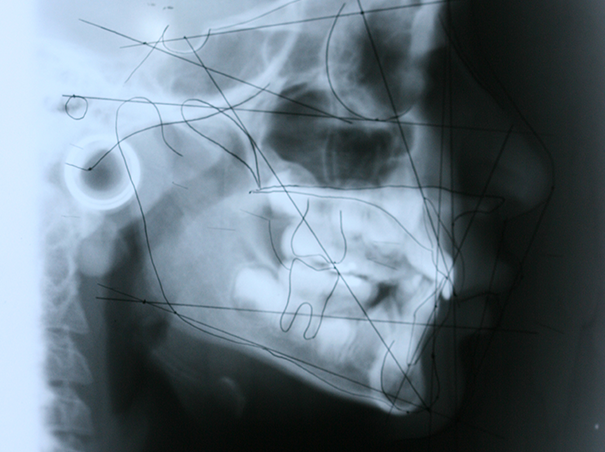

En la Clínica de Diagnóstico, el estudiantado tiene la oportunidad de integrar los conocimientos teóricos y aplicarlos para la correcta identificación de las enfermedades o patologías que puedan afectar las regiones oral y maxilofacial. Además de establecer un adecuado diagnóstico, manejar la condición y elaborar un plan de tratamiento para mantener la salud bucal de sus pacientes. También se realiza un tamizaje de cáncer bucal en el cual se examinan las zonas extraorales e intraorales de las personas pacientes para descartar zonas con lesiones potencialmente malinas o malignas. Aunado a esto, se hace énfasis en la educación al paciente sobre la prevención y detección temprana de cáncer bucal.

- Discutir casos clínicos y radiográficos donde se apliquen los conocimientos adquiridos a través de la carrera de Odontología.